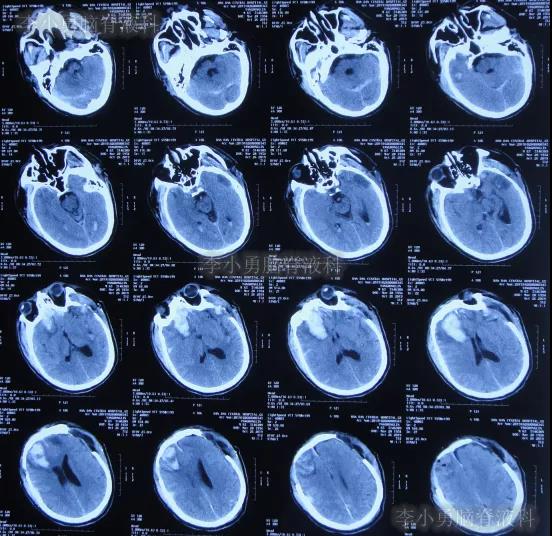

开颅术后第4天即2019年10月24日,查头颅CT示积血仍未明显减少(图-4)。

图-4:2019年10月24日头颅CT

继续治疗1周时间内,曾3次复查头颅CT(图-5、图-6、图-7)均示脑膨出逐渐加重的趋势,仍有积血;期间给予腰大池引流。

图-5:2019年10月26日头颅CT

图-6:2019年10月29日头颅CT

图-7:2019年10月31日头颅CT

图-8:2019年11月3日头颅CT